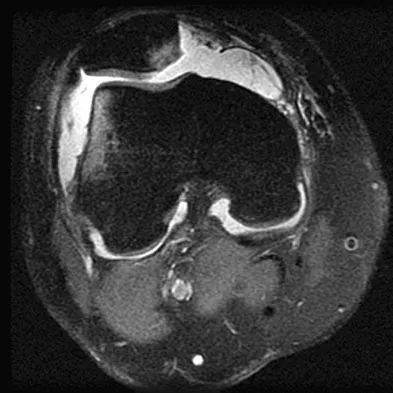

Figure 49 shows an acute axial MRI scan of a left knee. What is the most likely diagnosis?

Explanation